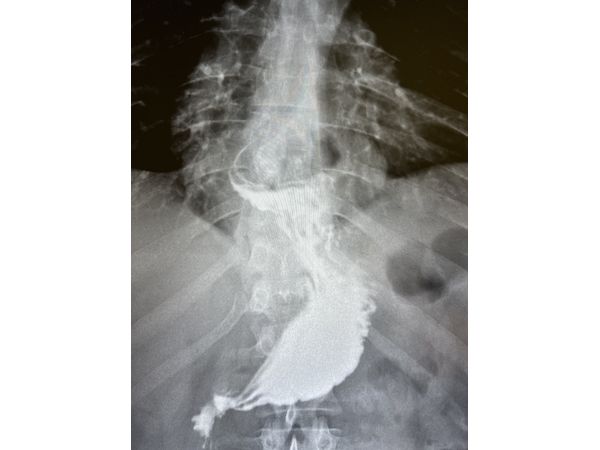

Вместо гастроскопии сделали рентгеноскопическое исследование пищевода, желудка и двенадцатиперстной кишки. По результатам удалось установить, что часть желудка расположена в грудной полости и зафиксирована в заднем средостении (между сердцем и позвоночником). Такое состояние соответствует фиксированной аксиальной кардио-фундальной грыже пищеводного отверстия диафрагмы.

Через месяц провели рентгенконтроль: грыжи не было, желудок расположен правильно (в брюшной полости). Гастроэзофагеального рефлюкса в положении Тренделенбурга (лёжа на спине, ступни немного выше головы) и стоя не выявлено.